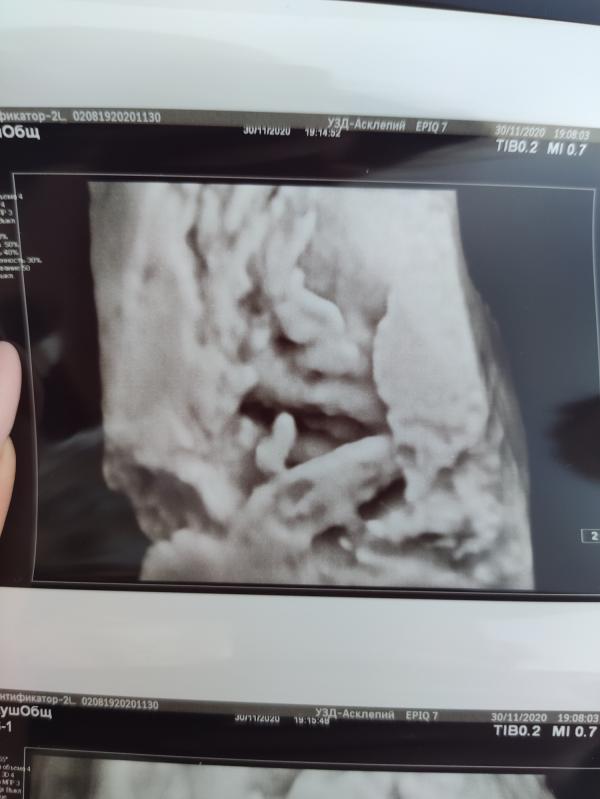

Ах эти сладенькие губки 😍 Кромки них ничего не хочет показывать, вредина 🤭

Носик еще видно))